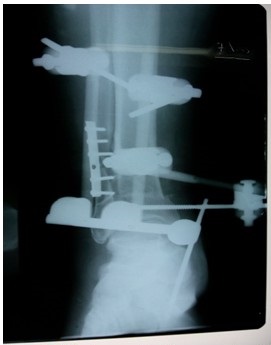

Como parte del plan quirúrgico trazado se realizó la limpieza quirúrgica requerida y se optó por la colocación de un fijador externo monopolar en puente para controlar la fractura del pilón, al montaje referido se le asoció una placa semitubular de un tercio de caña de seis perforaciones para estabilizar la lesión peroneal. (Figuras 4, 5, 6, 7).

La aplicación de la fijación externa en estas fracturas constituye un método fiable y validado por la literatura, la fijación del peroné con placa lateral posiblemente tiene sus aspectos negativos como son la posible consolidación en varo pero aporta muchos elementos positivos y por lo tanto preferimos su empleo asociado al fijador externo monopolar en puente.

En este caso fue empleada la fijación del primer metatarsiano con el objetivo de evitar el equino del tobillo. Existen otras opciones terapéuticas y la aplicación de cada una de ellas está sujeta a la disponibilidad de los recursos en cada institución y a la experiencia en la aplicación de estos métodos por parte del equipo médico.